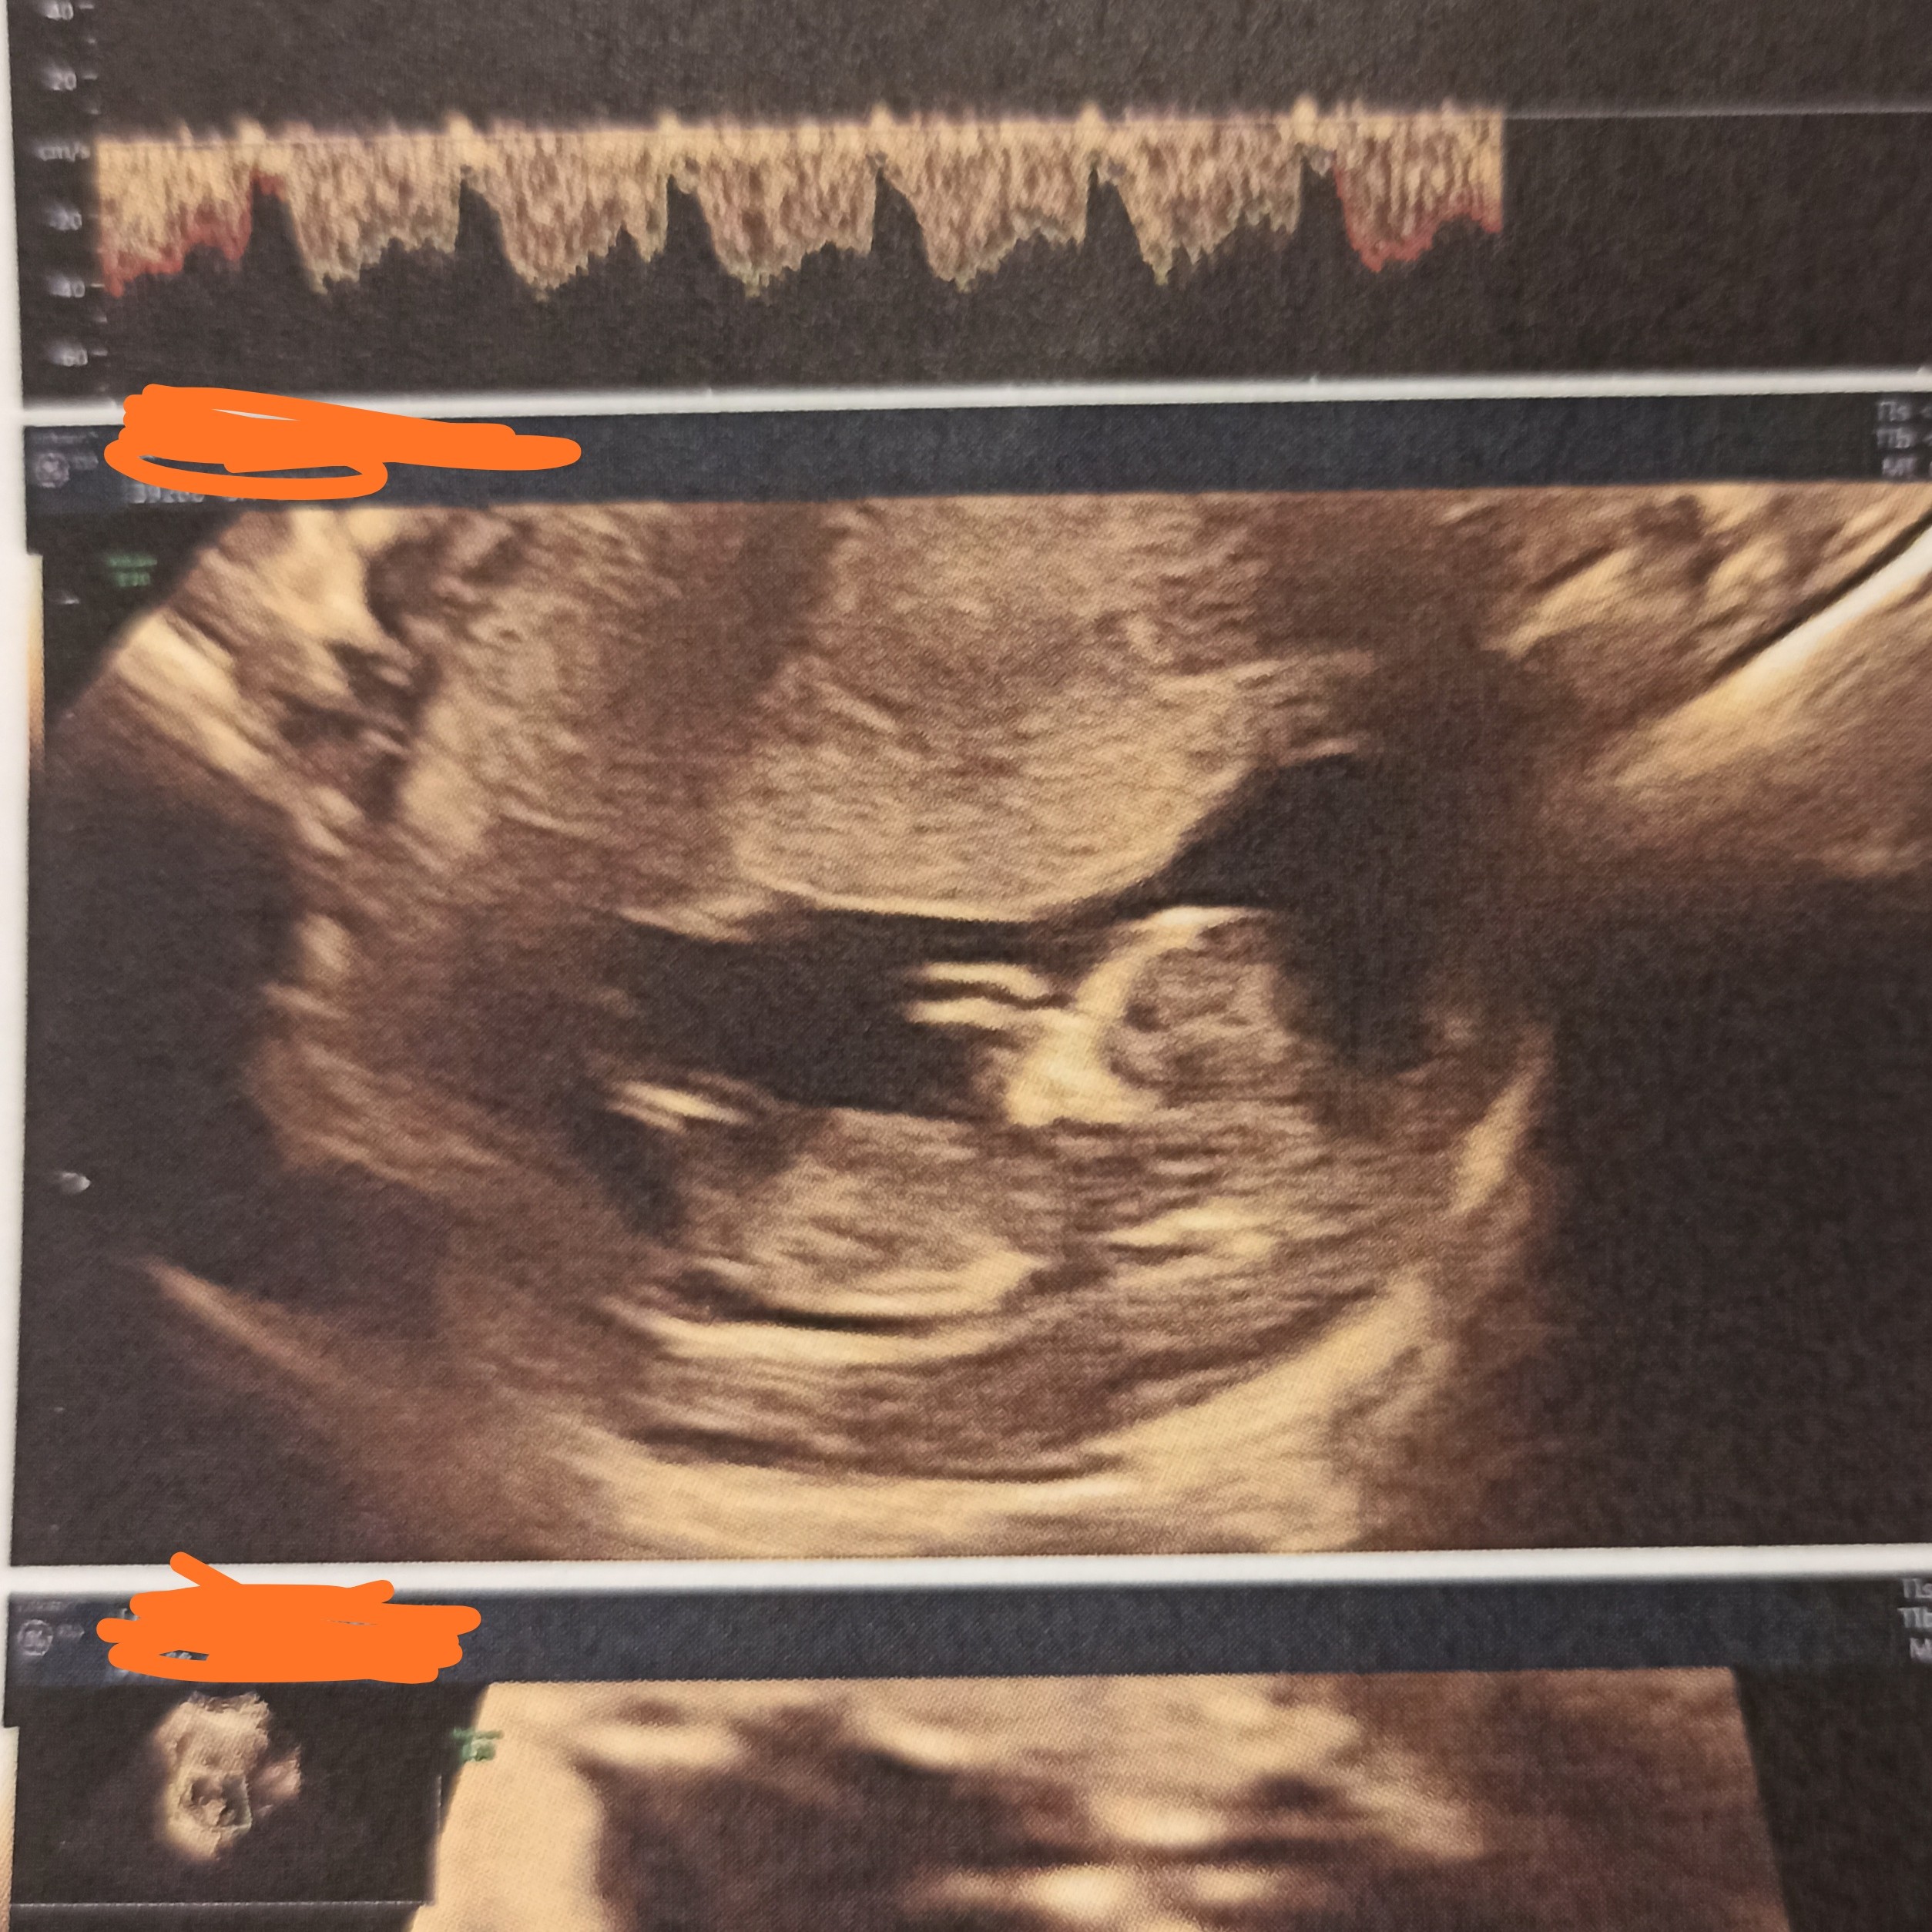

Który tydzień?Witam serdecznie, czy widać na tych Usg płeć dziecka ?

12+4Który tydzień?

11+6 to za wczesnie na ocenę wyrostka płciowegoDzień dobry. Czy na tych zdjęciach widać już płeć? Jak myślicie ?![]()